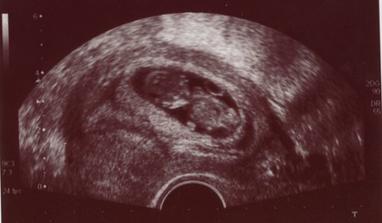

Čekání na Kateřinku... (UZ)

Čekáme holčičku - Kačenku. Dokud jsme jméno vybírali, říkali jsme jí Melounka. I.TP máme 29. 2., II.TP 2. 3. 2008. a III.TP je 13. 3. 2008.